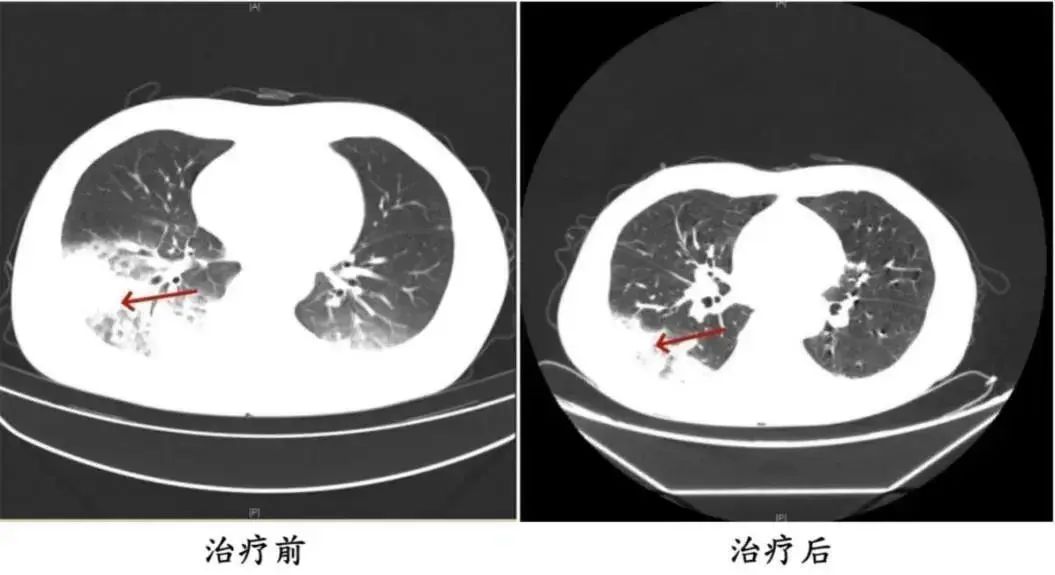

△治疗前后陈先生肺部CT影像。

据医生说,李先生吹了三天空调后,开始出现肌肉疼痛、头痛、发热、咳嗽等症状。一开始他以为只是感冒,但是吃了感冒药就没效果了,反而越来越严重。住院后,胸部CT显示,李先生的左肺已经出现了大面积的白色图像,几乎占据了肺的一半。经检测,最终确认为嗜肺军团菌肺炎。

不仅是家用常规空调,久未清洗的汽车空调也可能成为细菌的“苗床”。湖南的陈先生开车出差时,因为天气热,开了一台很久没清洗的汽车空调。他每天在车里呆十几个小时,回来后出现了类似李先生的疾病。经检查,也诊断为军团菌肺炎。